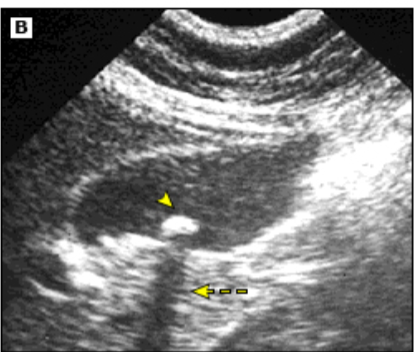

Endoscopic US

Endosonographic image of stone in common bile duct (with acoustic shadow)